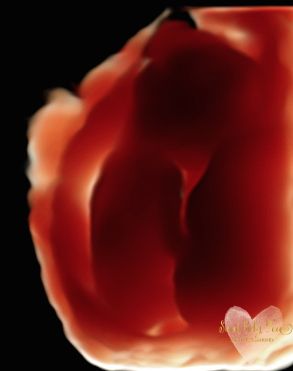

3D/4D/5D Ultrasound Gallery

Take a peek at our Photo Gallery. All of our 2D, 3D, 4D, HD elective ultrasound images are truly ours. They come directly off our machine from our highly trained staff. We can start getting great 3D/4D images as early as 10 weeks!